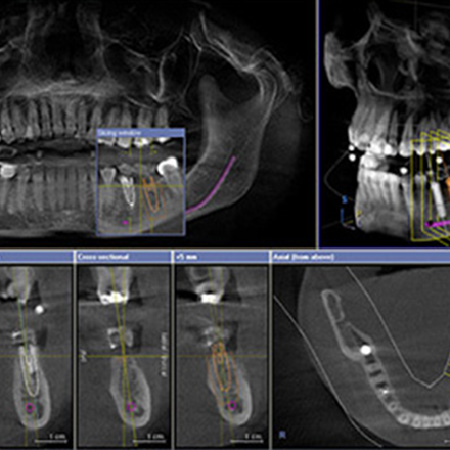

●3Dシミュレーション

CTで撮影した画像を元に、インプラントを骨にどの角度でどの位の深さで埋入するかを3次元でシミュレーションします。